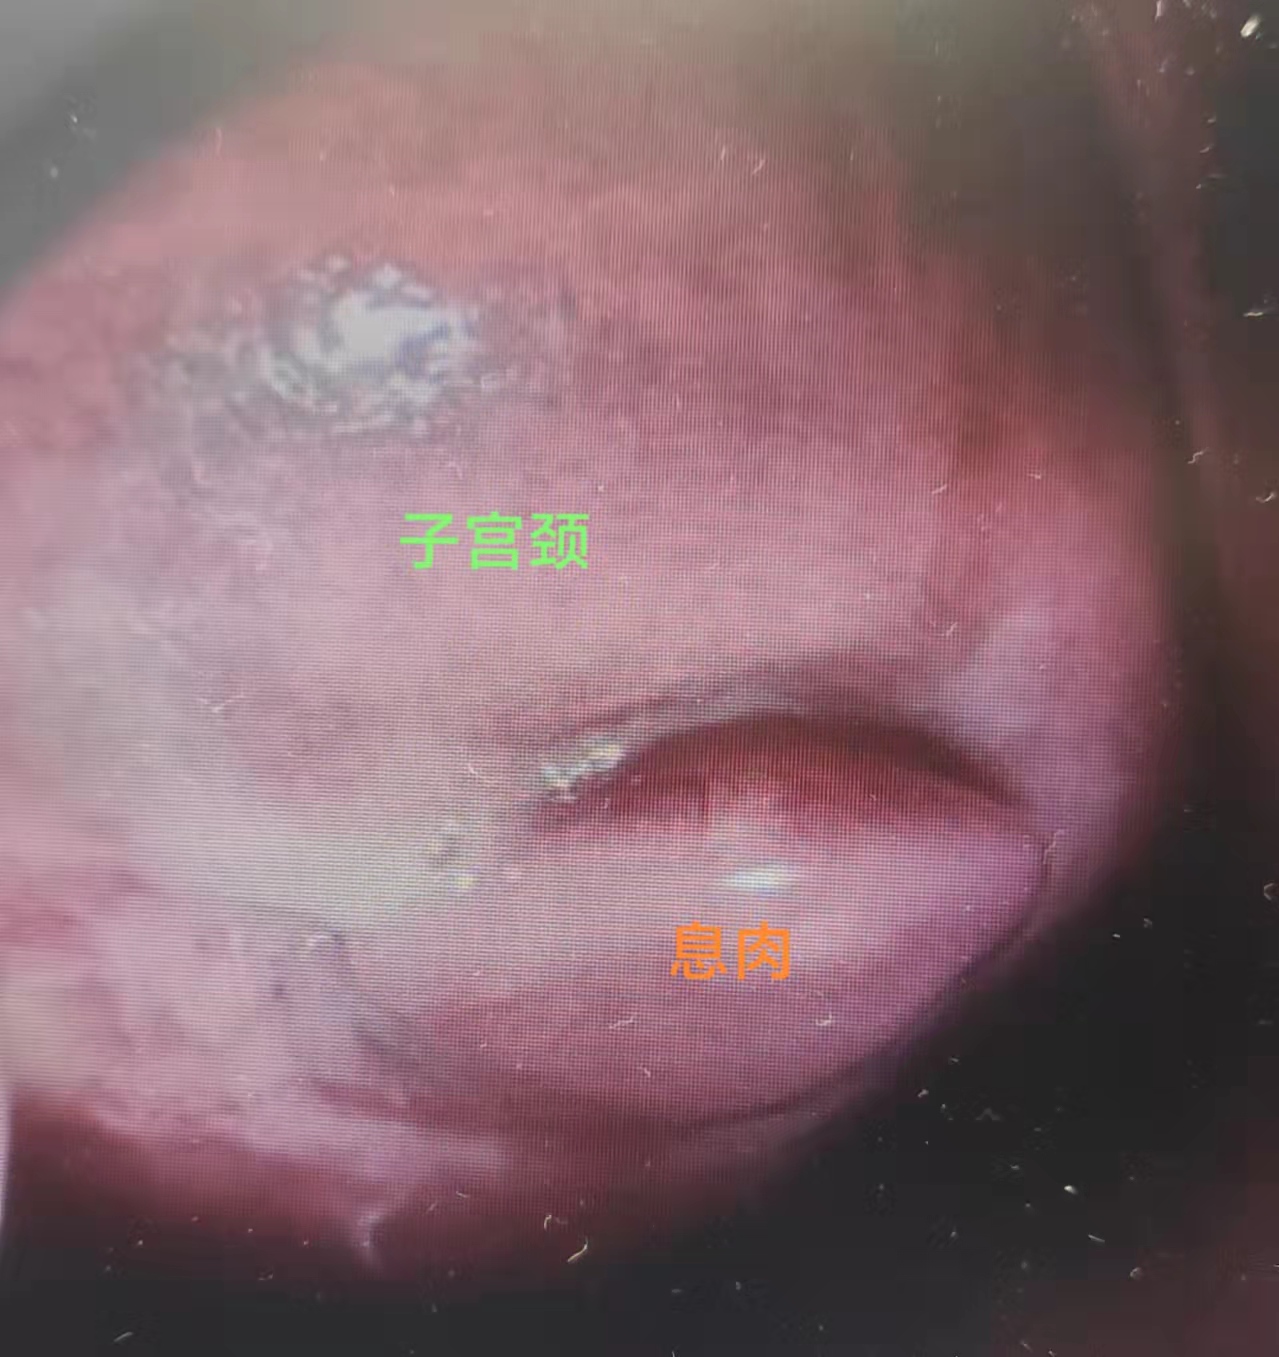

如妇科的息肉,其有阴道壁息肉、子宫内膜息肉、子宫颈息肉,一般症状不明显。在不孕就诊、妇科检查或B超时发现。也有一部分人有如下症状求诊。

一、宫颈、阴道息肉是宫颈阴道慢性炎症的一种,药物只是起辅助治疗,以手术摘除为主,可行息肉摘除术或电切术。

子宫颈息肉